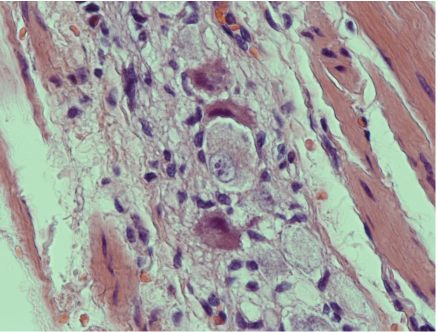

Histopathological examination of sections from the partial gastrectomy specimen showed large collections of ganglion cells lying in between the hypertrophied muscularis propria. The described ganglion cells were large, had dense eosinophilic cytoplasm with enlarged nuclei and prominent nucleoli. Their numbers varied between 5-15 ganglion cells per one medium to high power microscopic field, and were surrounded by hypertrophied nerve bundles with areas of edema and fibrosis, (Figs. 2A,B).

Figures 2B: Gastric ganglioneuromatosis and hypergangliosis due to intestinal neuronal dysplasia type II. Note the presence of abnormal neurons within hyperplastic nerve bundles. Hemotoxylin and Eosin stain × 400.

These findings were confirmed by immunohistochemical stains which included S-100 protein and neurone specific enolase. A final diagnosis of gastric hyperganglionosis (also referred to as neuronal dysplasia type B) and diffuse ganglioneuromatosis was made. This diagnosis was based on the abnormal presence of numerous giant ganglion cells associated with many bundles of hypertrophied nerve fibers and Schwann cells. These changes are usually associated with hypertrophied muscularis propria which may lead (as in this unusual case) to pseudo-obstruction of the gastric outlet mimicking pyloric stenosis secondary to a neoplastic process.